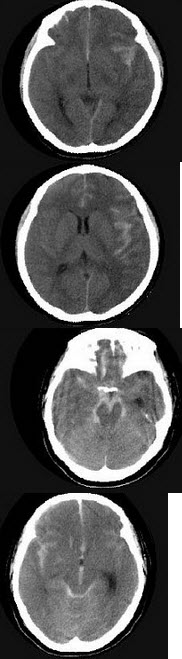

女,37岁,产后10天出现剧烈头痛头昏伴神志不清2天,请根据所提供图像,选择最可能的诊断( )

A:右侧蛛网膜下隙出血

B:右侧脑膜脑炎

C:右侧硬膜下血肿

D:右侧脑梗死

E:右侧静脉窦血栓形成